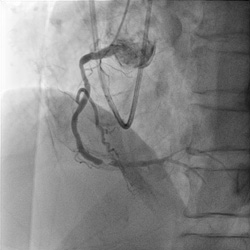

下肢動脈血管形成術

治療前   治療後